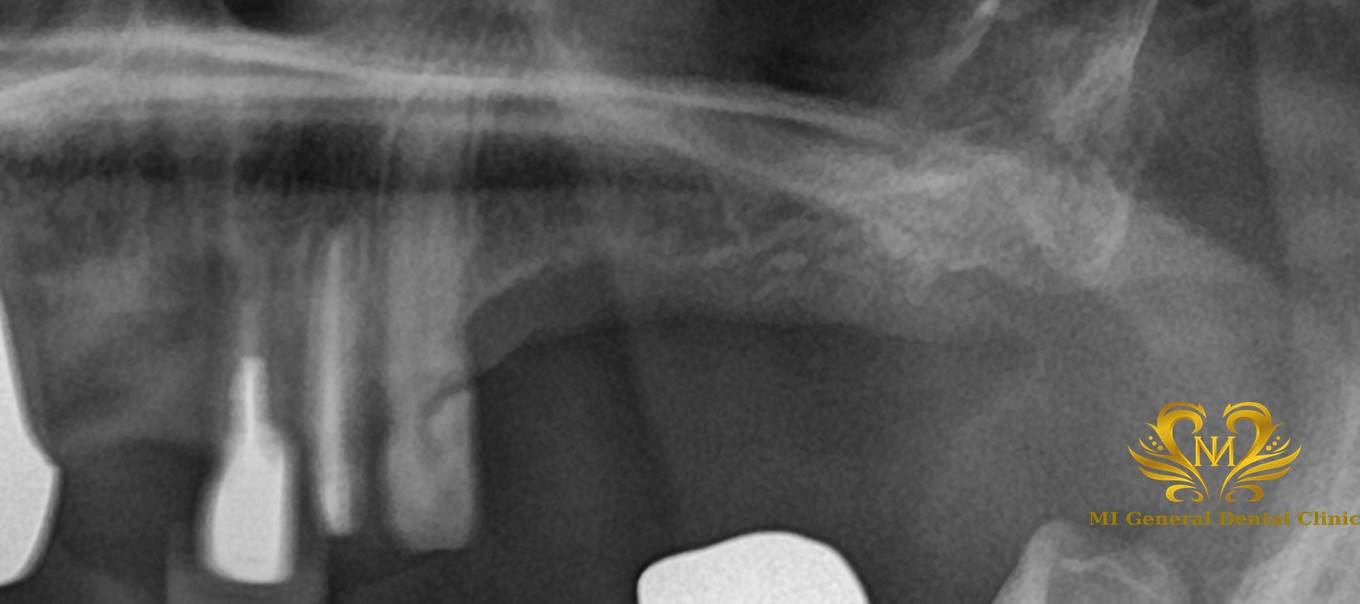

治療前

義歯を使っていたが、コロナ禍でマスクをしていたこともあり、義歯が合わずはめていなかった。

| 主訴 | 義歯を使っていたが、コロナ禍でマスクをしていたこともあり、義歯があわずはめていなかった。そのため、人前で笑うことができなかった。 インプラントの話は3年位前から聞いて考えていた。 |